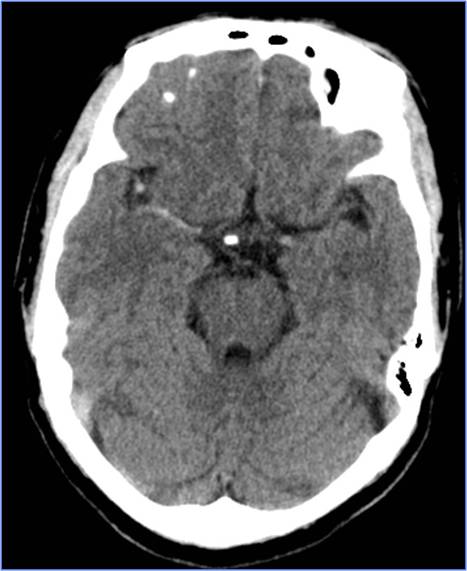

Case8 风心病、心脏瓣膜病脑栓塞

》58岁,女性,既往风心病、房颤、心脏瓣膜病

》因“活动后心慌胸闷5年”于心外科住院,拟行心脏瓣膜置换术

》12:30出现言语不清、左侧肢体无力,NIHSS 18分

》13:00完成头CT检查

》请神经内科会诊,转科 Ø14:00行股动脉穿刺

》15:15结束手术

》16天后出院,NIHSS 2分

再发脑栓塞

》6月份行二尖瓣、主动脉瓣置换术

》7:50出现言语不清、左侧肢体无力,NIHSS 25分

》9:10完成头CT检查

》9:35行股动脉穿刺

》10:05结束手术

》10天后出院,NIHSS 3分

》原因:服用华法林不达标,INR 1.31

▼术前头MRA

▼术后24小时CT